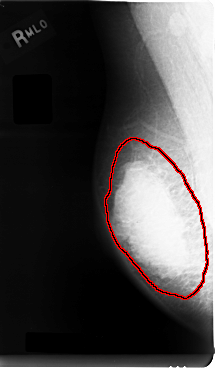

C_0005_1.RIGHT_MLO

FILE: C_0005_1.RIGHT_MLO.OVERLAY

TOTAL_ABNORMALITIES 1

ABNORMALITY 1

LESION_TYPE MASS SHAPE LOBULATED MARGINS MICROLOBULATED

ASSESSMENT 5

SUBTLETY 5

PATHOLOGY MALIGNANT

TOTAL_OUTLINES 1

BOUNDARY